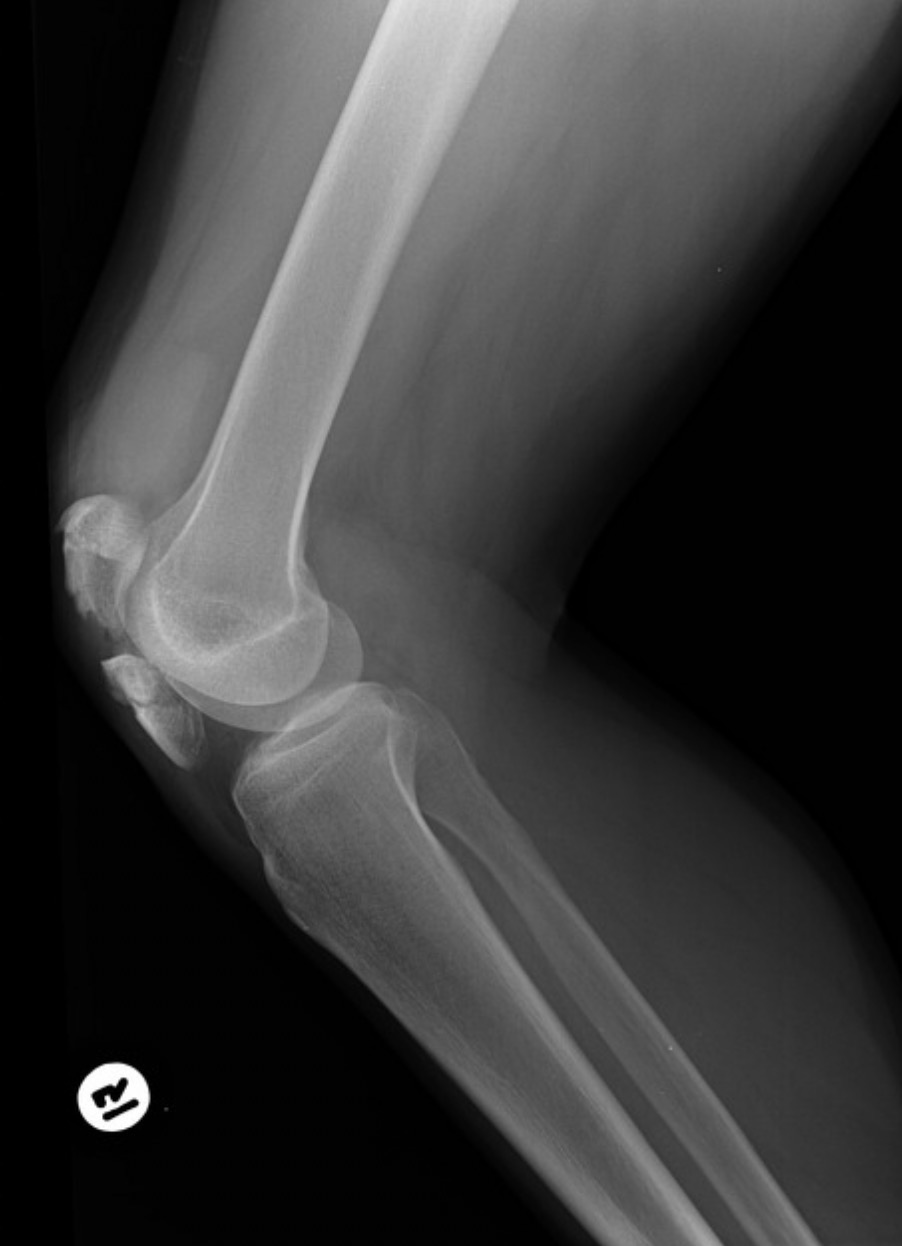

Name the projection.

Should it be repeated, if so why?

Lateral Knee.

No.

Ignoring pathology and other factors - Is the tube angled appropriately in this image?

No. The femoral condyles are not superimposed, indicating no tube angle.

Is the patient in true lateral with proper tube angle? Explain.

True lateral: No. Patient is under rotated. Fibular head too anterior.

Tube angle: No. Femoral condyles not superimposed.

True lateral: No. Patient is over rotated. Fibular head too posterior.